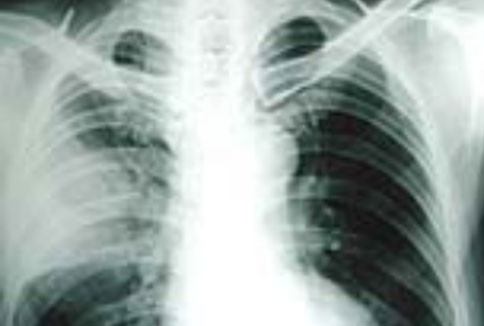

Đề phòng viêm phổi khi chuyển mùa

Viêm phổi là bệnh nhiễm trùng rất thường gặp, nhất là ở người cao tuổi do sự lão hóa của hệ thống bảo vệ miễn dịch. Khi thời tiết chuyển mùa, các bệnh mạn tính như bệnh phổi tắc nghẽn mạn tính, đái tháo đường là điều kiện thuận lợi cho các tác nhân gây bệnh như virus, vi khuẩn, nấm và ký sinh trùng xâm nhập và tấn công phổi gây nên bệnh viêm phổi.

Bệnh viêm phổi là căn bệnh có tỉ lệ người mắc rất cao và có thể gây tử vong. Mức độ nặng nhẹ còn phụ thuộc vào các tác nhân gây bệnh, độ tuổi cũng như tình trạng sức khoẻ của mỗi người.